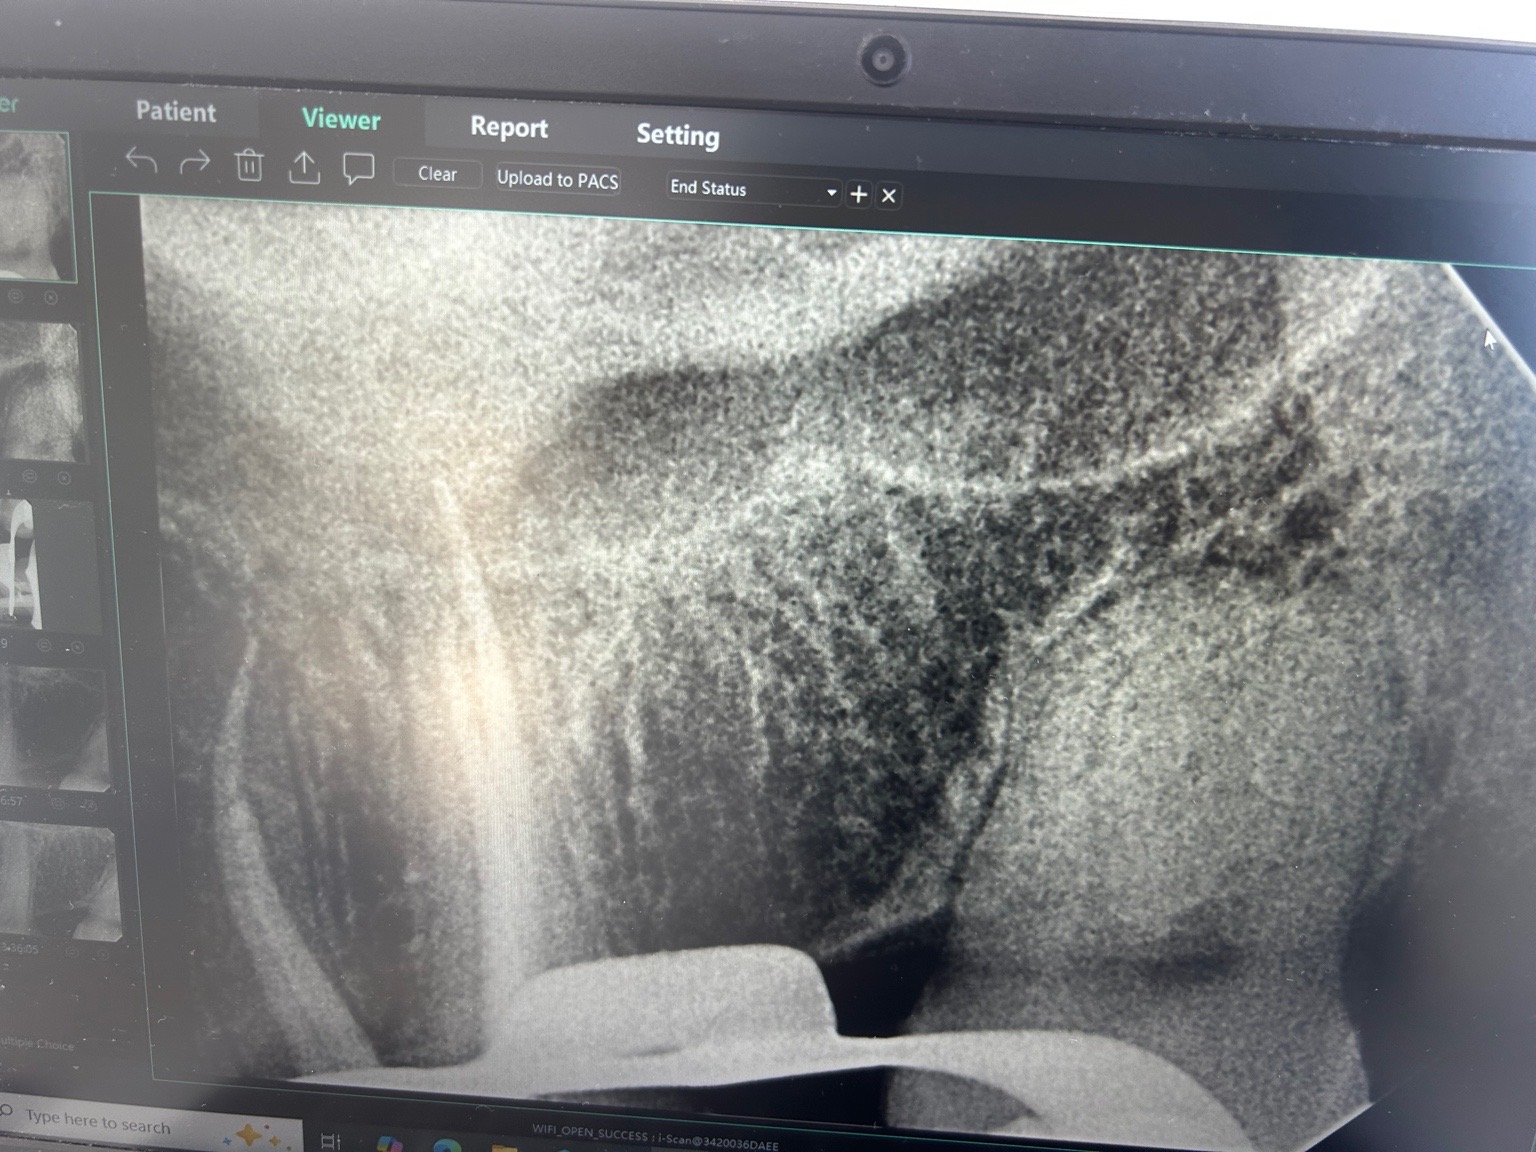

Initieel licht gevoelig aan kiezen. 1 maand. Koud alleen. Smeren tandpasta advies. Vorige week pijn. Diffuus moeilijk te pinpointen. Gevoelsmatige was het verstand kies. Daarna 6. Licht breuk lijn in 6 niet zichtbaar. Pijn 2 dagen. 1 dag diffuus kloppend. Koud test normaal. Foto gemaakt. Pijn trok weer weg. Geen wkb nodig. Afgelopen maandag test met bijt. 6 gevoelig met houten bijt test maar nog steeds geen beeld passend bij irreversible pulpitis. Tandarts vermoed sinus infectie op basis van deze foto. Gisteren en vandaag percussie gevoel weg na start behandeling neusspray. Pijn vandaag max. 1 tussen 1 en 10 2 tandartsen bekeken. Eentje niks over sinus andere wel. Helpt dit?

Om de sinus beter te bekijken zou ik een ander foto, een opt (panorama) willen hebben waarop de hele sinus te zien is en ook te vergelijken met de andere zijde. Op basis v deze foto is mogelijk een versluiering te zien maar zou dat zo niet in verband kunnen brengen met een sinusitis. Als u voorover buigt voelt u een klotsend gevoel in de neusholte.

Ik zie mogelijk een verbreed parodontaal spleet ( lijn tussen kies en tandvlees voor de leek) in de 25. Lijkt op een "diepe"vulling (dicht bij de zenuw)... hoe test de 25...Bij twijfel kan je eventueel proef boren zonder verdoving maar dat is niet altijd betrouwbaar. Knarst u??.

Tandarst vond de sluiering inderdaad een mogelijkheid, uiteraard niet definitief. Maar door koude test bijten op houten brokje zag hij niet echt een probleem met zenuw. k had wel sinus gerelateerde klachten. 2 a 3 weken geleden zware verkoudheid. Kreeg wel drukkend hoofdpijn. Klotsen gevoel neen, maar ik merkte wel druk gerelateerde perikelen maar negeerde ze. Focus was pijn :)